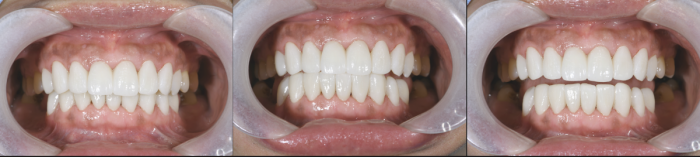

修復後、有益な口腔内機能が観察されました。